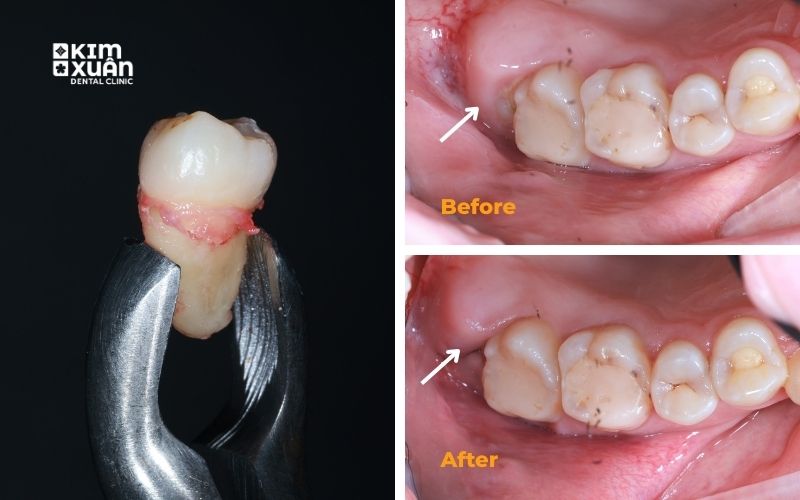

7. Nhổ Răng Khôn An Toàn - Tại Nha Khoa Kim Xuân Bình Thạnh - TP. HCM

Tại Nha khoa Kim Xuân, nhổ răng khôn được thực hiện theo quy trình chuẩn y khoa, đặt yếu tố an toàn và trải nghiệm khách hàng lên hàng đầu. Mỗi trường hợp đều được đánh giá kỹ lưỡng để đảm bảo nhổ răng hiệu quả, hạn chế đau và tránh biến chứng.

Quy trình nhổ răng khôn bao gồm:

Thăm khám tổng quát và chụp phim X-quang trước khi nhổ

Bác sĩ trực tiếp đánh giá vị trí răng, mức độ khó và nguy cơ liên quan

Thực hiện nhổ răng nhẹ nhàng, hạn chế xâm lấn mô mềm

Tư vấn rõ ràng chi phí nhổ răng khôn trước khi thực hiện, cam kết minh bạch

Không phát sinh chi phí - kiểm soát đau tốt - hồi phục nhanh, giúp khách hàng yên tâm trong suốt quá trình điều trị.